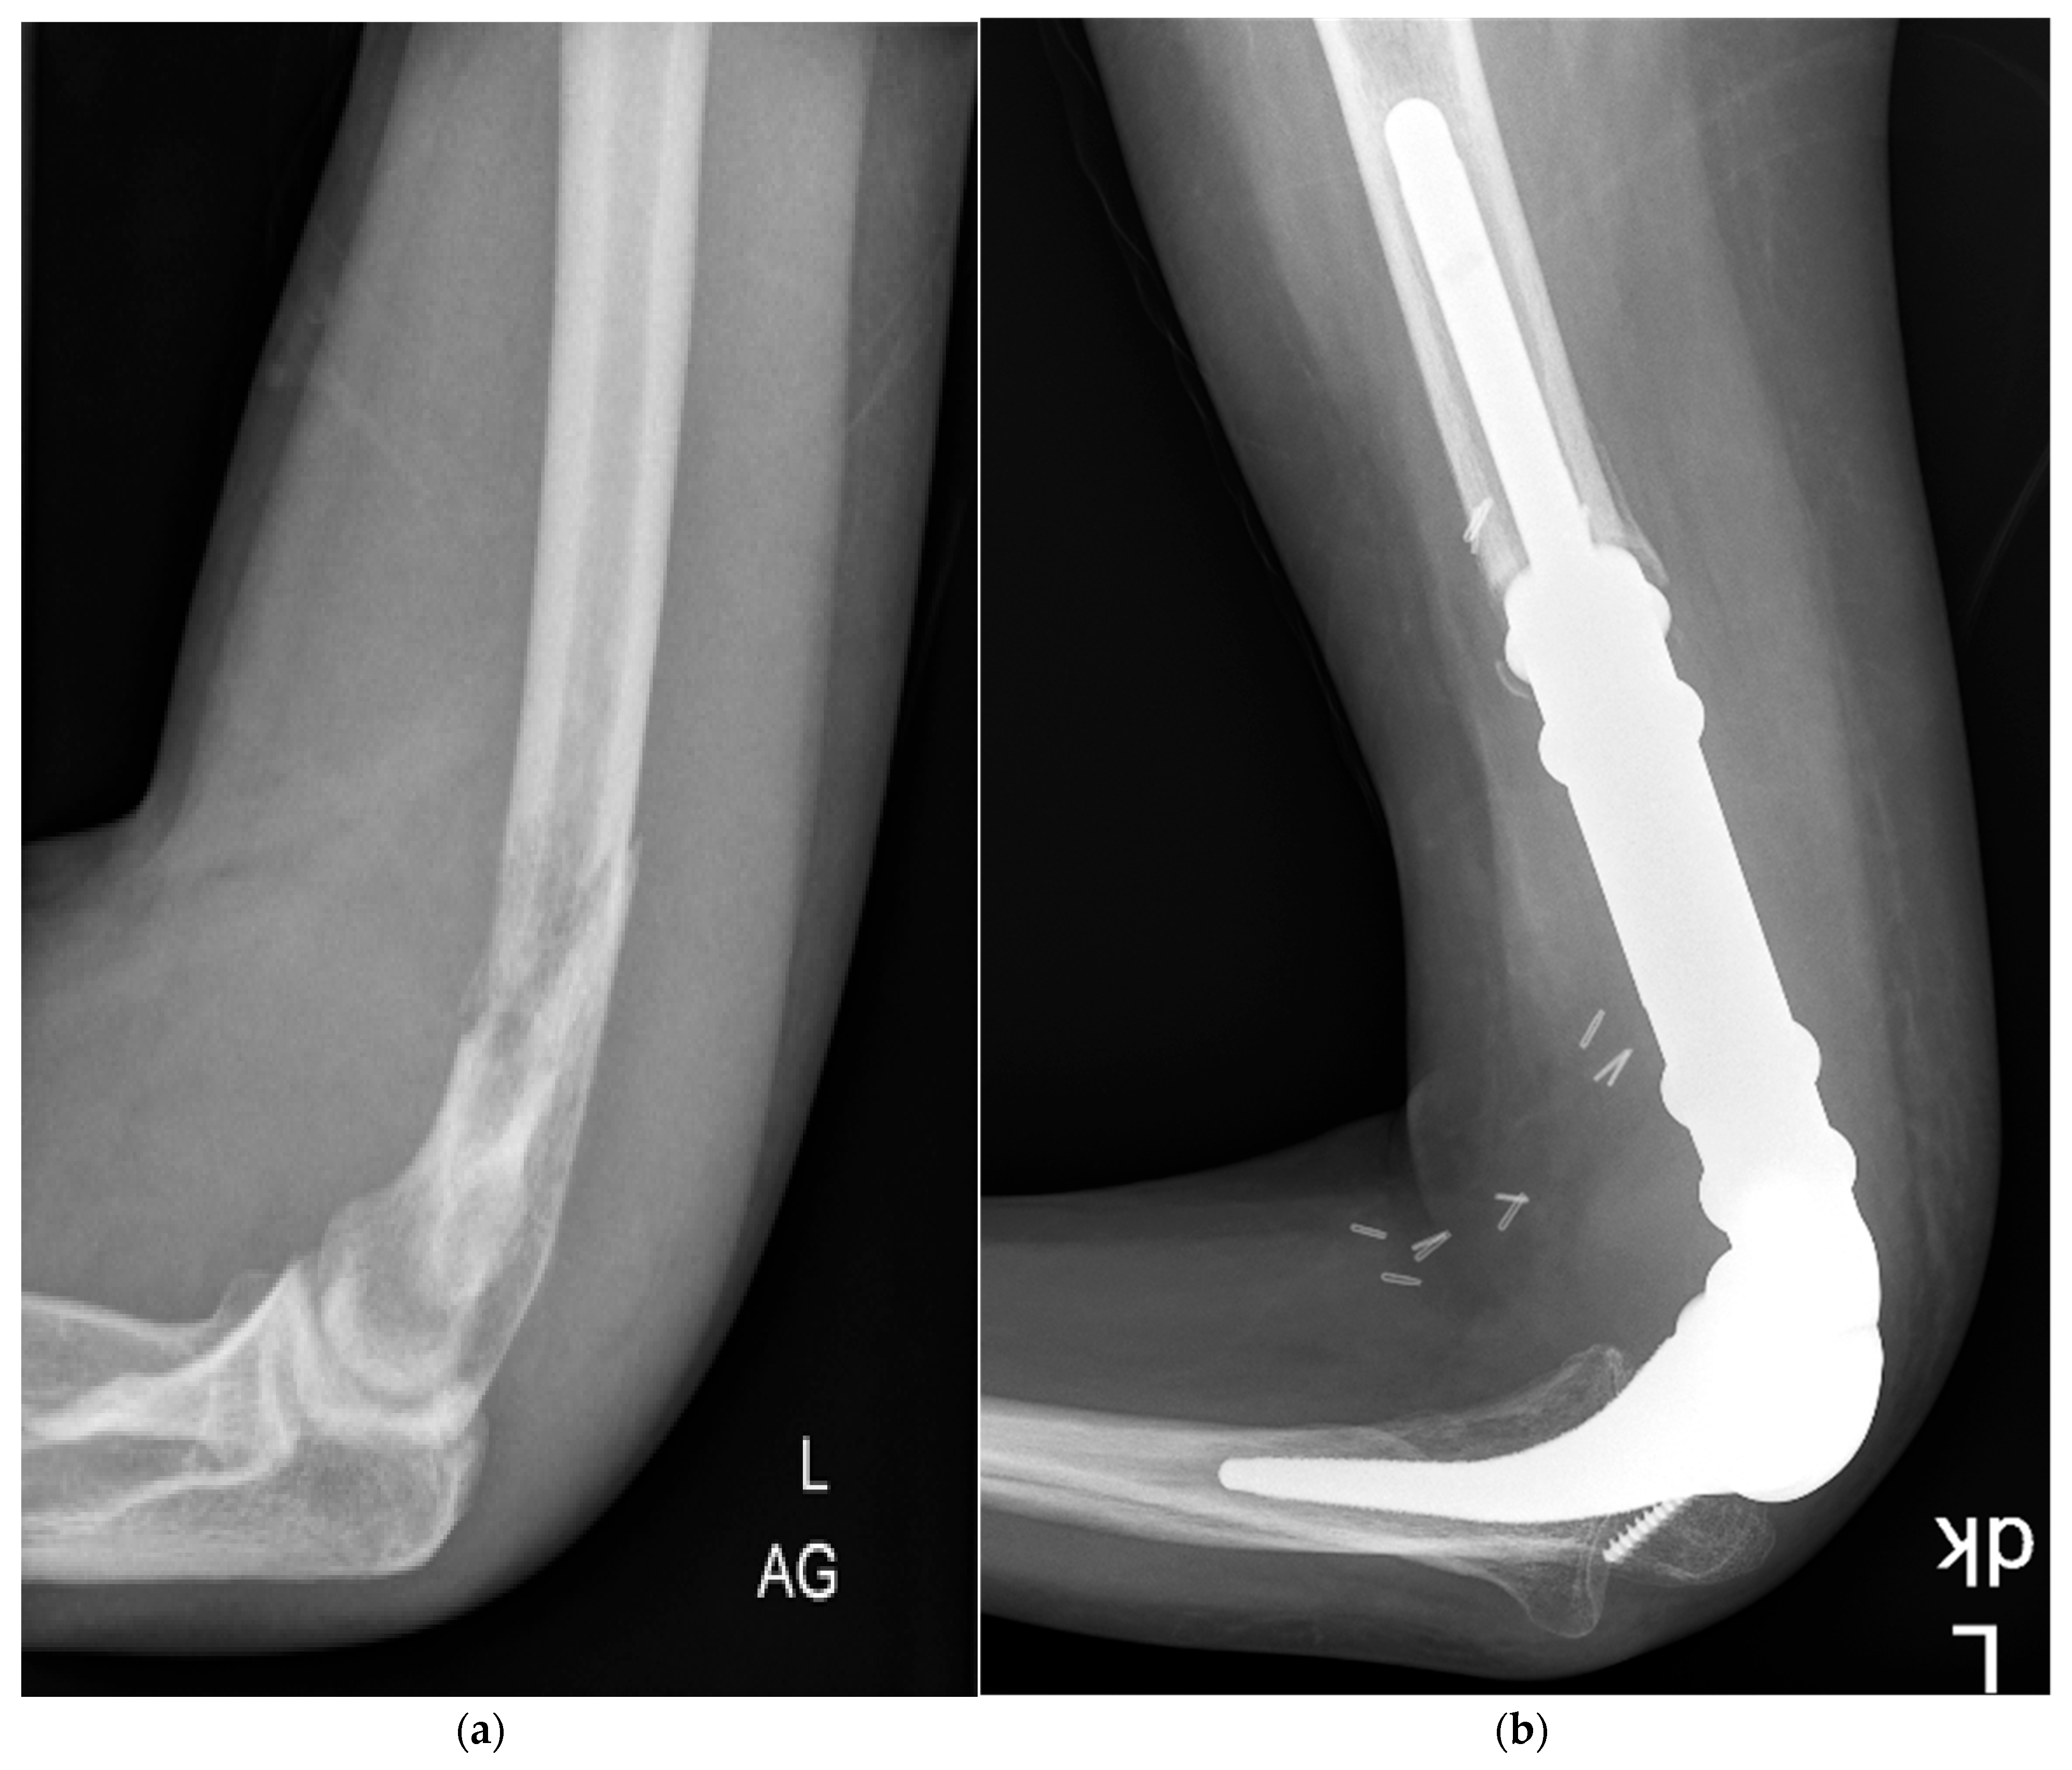

2.1. Surgical and Implant Details